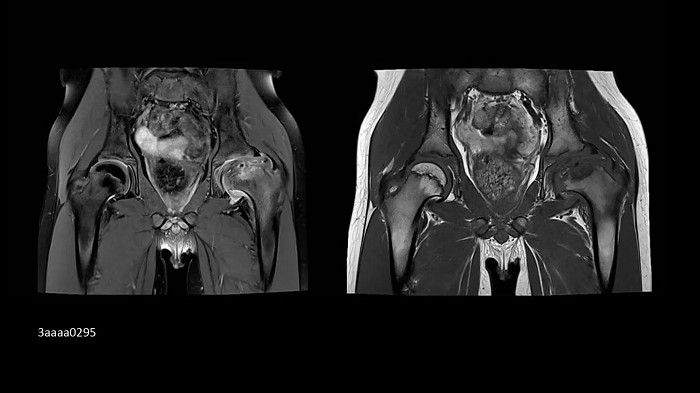

Hip imaging with the new Ultraflex Coils

In pediatrics, high-resolution bilateral hip imaging with the new UltraFlex Coils was performed on an 8-year-old boy.

Image Credit: Radiologie Miinchen Harlaching, Munich, Germany